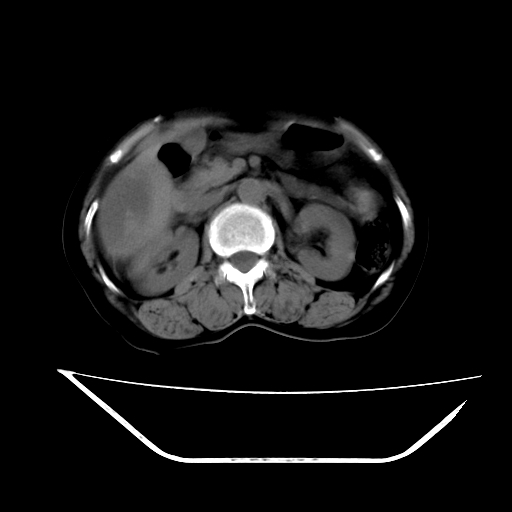

2008-6-10ct平扫

6月份ct片显示肝内巨大混杂密度团块,伴包膜下积液(内含液液平面),增强多无明显强化。只能考虑肝占位病变,并肝内、血膜下血肿。肝ca并出血多见,而肝血管瘤并破裂出血少见。

6月份ct片显示肝内巨大混杂密度团块,伴包膜下积液(内含液液平面),增强多无明显强化。只能考虑肝占位病变,并肝内、包膜下血肿。肝ca并出血多见,而肝血管瘤并破裂出血少见。